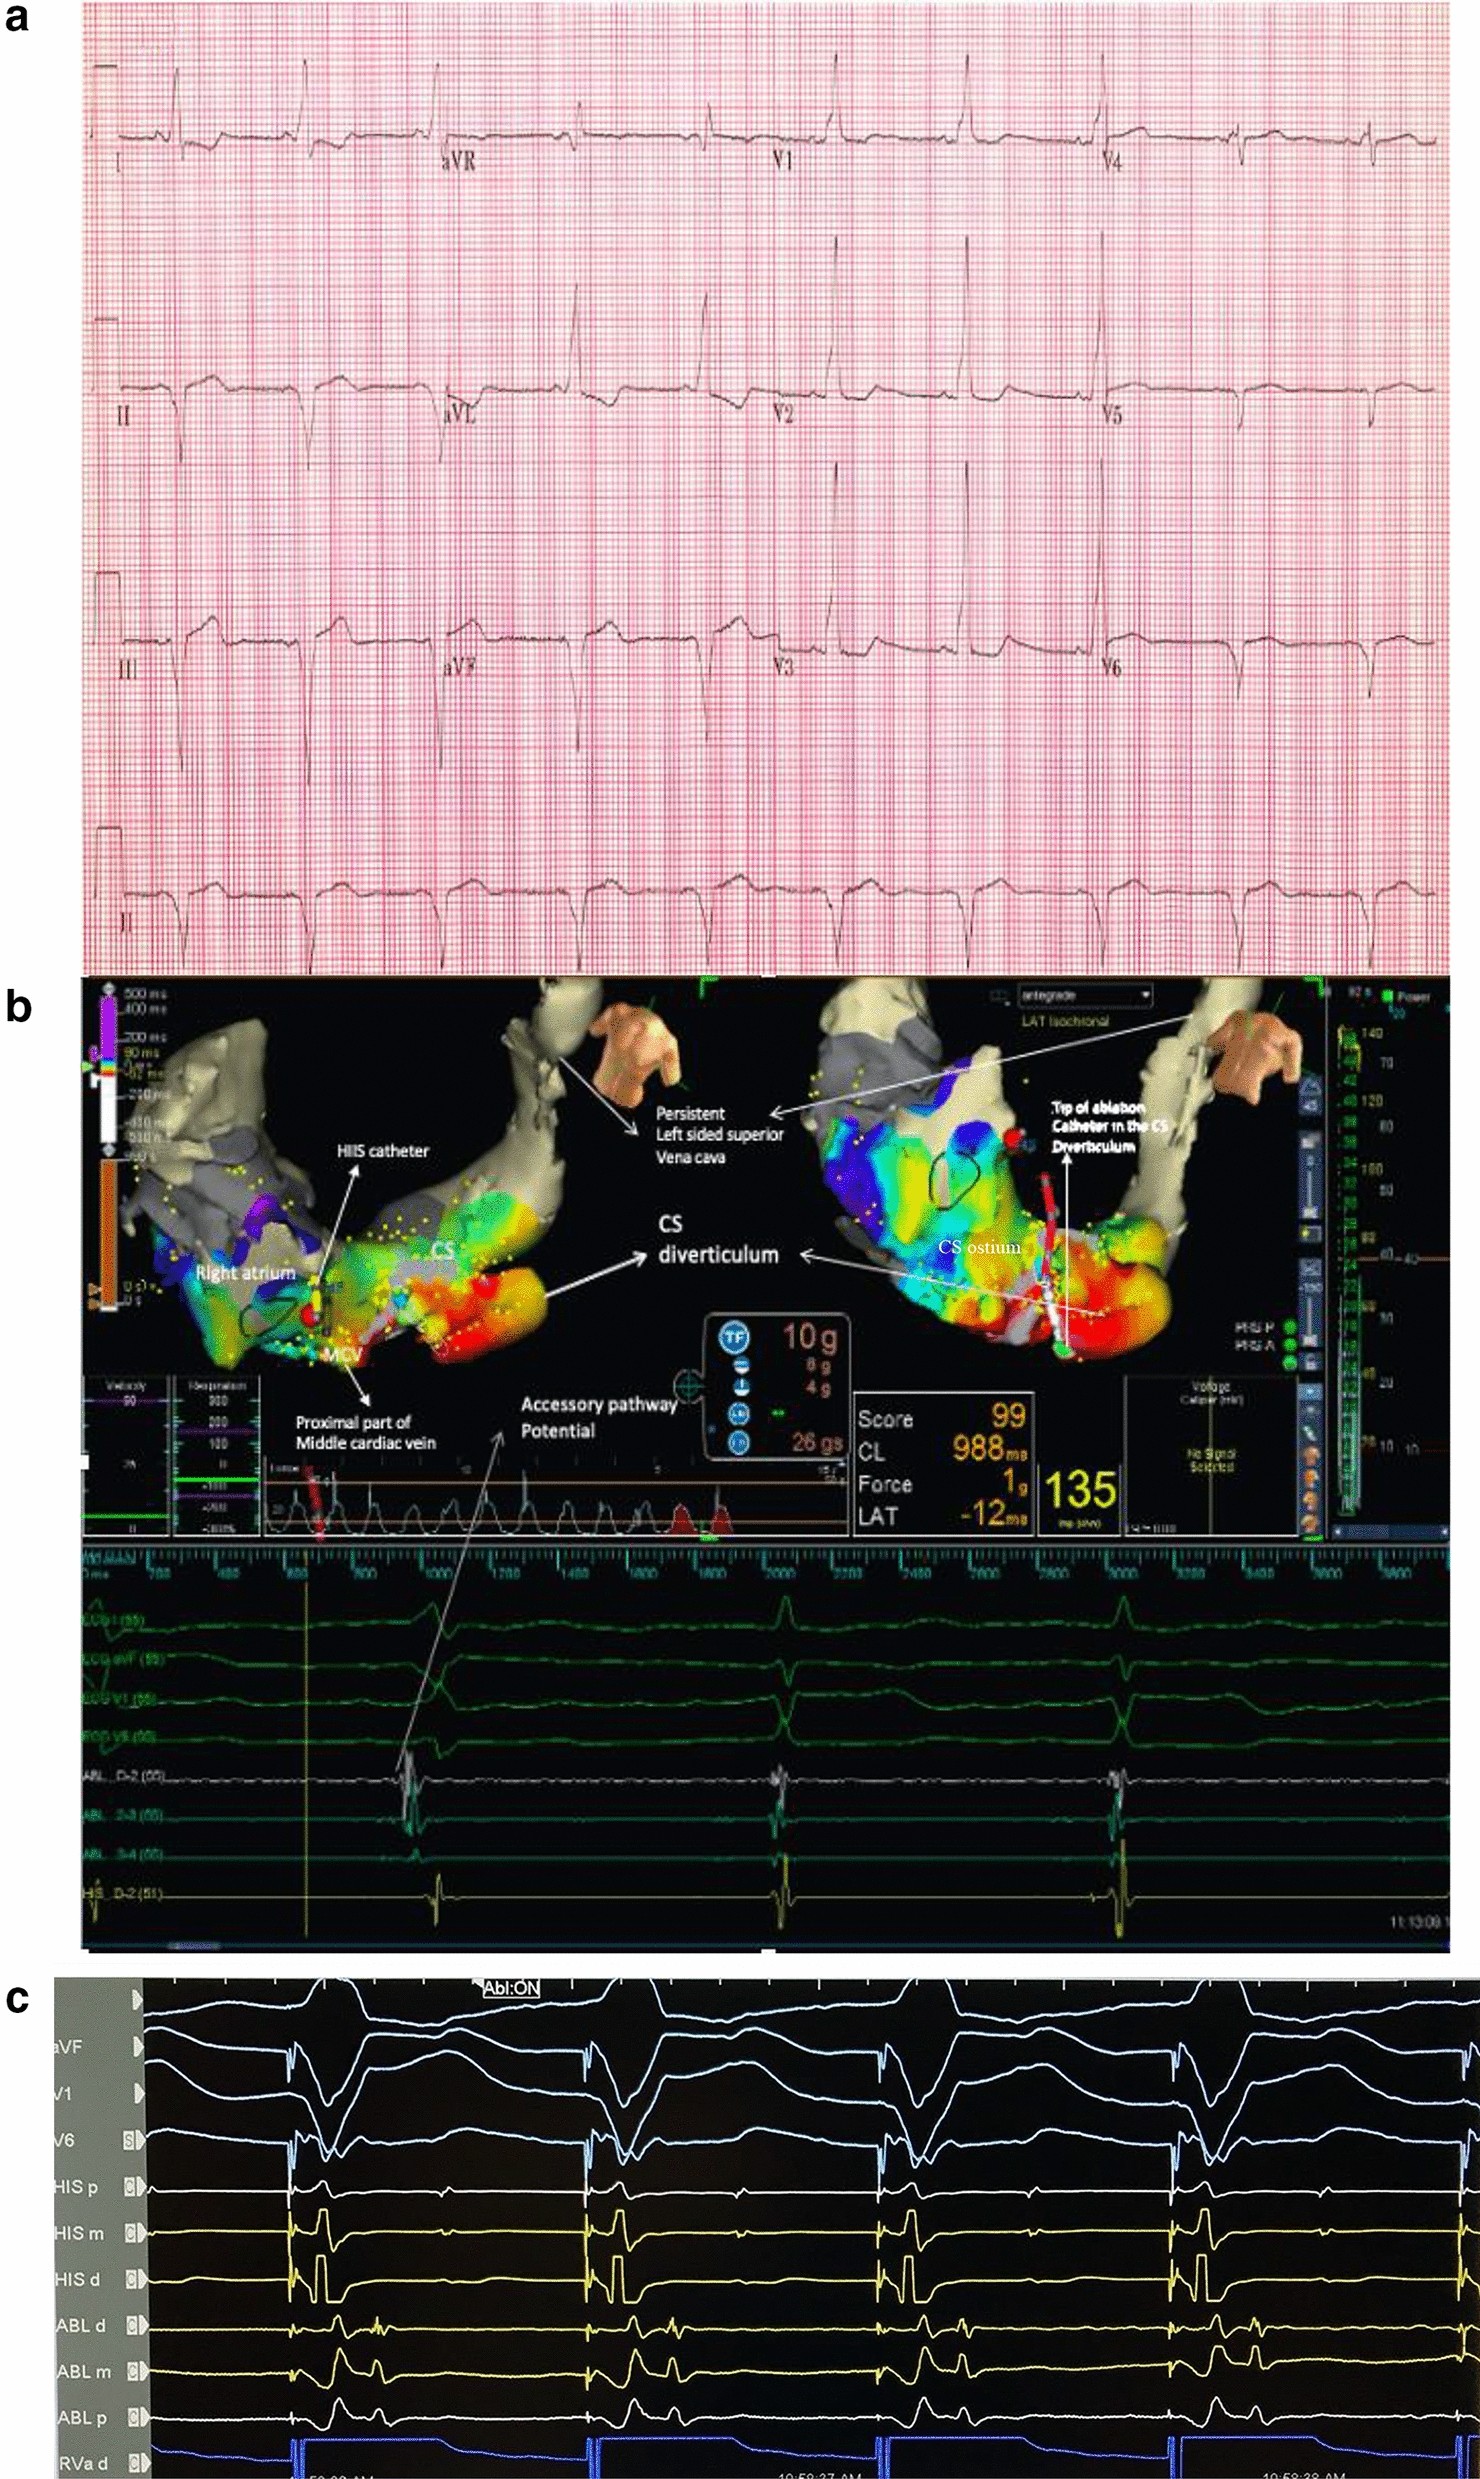

Fig. 1

a Surface EKG shows ventricular pre-excitation with negative delta wave in limb lead II consistent with posteroseptal AP. b The AP potential can be seen between atrial and ventricular electrograms (long white arrow). The disappearance of the AP potential and loss of ventricular pre-excitation during RF ablation is demonstrated. The tip of ablation catheter is shown to be in the CS diverticulum where the earliest local ventricular EGM in relation to the delta wave was detected. c Retrograde mapping of the AP during ventricular pacing. The distal ablation catheter was in the CS diverticulum. The local atrial EGM detected on ablation catheter was earlier than atrial EGM on the HIS catheter. MCV: middle cardiac vein